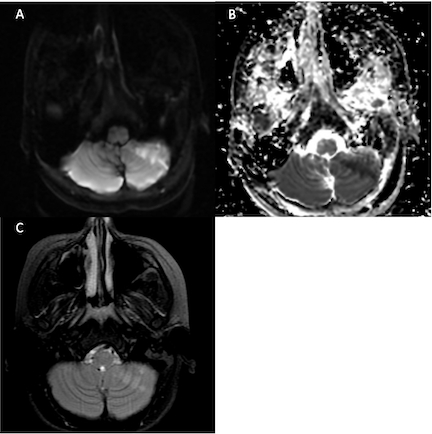

Neurologic exam showed subtle left-sided ataxia on heel-to-shin testing; finger-to-nose testing was intact. He had unstable, wide-based gait requiring assistance to ambulate, and was unable to tandem walk. Romberg was positive with sway. The remainder of the exam was normal. Initial MRI demonstrated an acute/subacute left cerebellar hemisphere infarct in the posterior inferior cerebellar artery territory. Laboratory evaluation was unremarkable and included CBC, CMP, CRP, ESR, coagulation studies and hypercoagulability labs. Transthoracic echocardiogram was without evidence of left-to-right shunt.

CTA demonstrated subtle narrowing of the left vertebral artery (VA) at the atlantooccipital joint with asymmetry in the position of the dens relative to the lateral masses of C1, raising concern for dynamic vessel compression. TCD with and without neck rotation and flexion/extension radiographs of the cervical spine were non-diagnostic. Given ongoing concern for rotational vasculopathy, the patient was started on aspirin 81 mg and was placed in a soft cervical collar with plans for further imaging once he had recovered from his acute stroke. Eight weeks later, he underwent contrast-enhanced MRI/MRA of the head and neck with dynamic positioning, which re-demonstrated left VA narrowing at the occipital condyle-axis joint with focal narrowing when piercing the dura. MRA in 8 positions demonstrated loss of flow-related enhancement with left head tilt and neck extension. A new area of T2 hyperintensity was visualized on MRI in the left cerebellum, likely representing an interval infarction. He subsequently underwent a C1 laminectomy without complication fourteen weeks after his initial presentation.